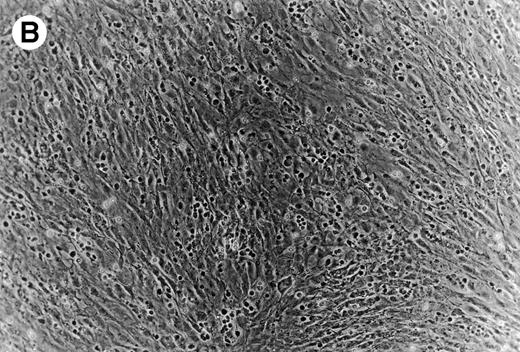

(A) Representative phase contrast photomicrograph of pseudoemperipolesis of CLL B cells after 2-hour culture on the heterologous murine stromal cell line, M2-10B4. Cells that had not migrated beneath the stromal cells washed off, and the stromal cell layer containing the migrated CLL cells was photographed (200x magnification). Pseudoemperipolesis is characterized by the dark appearance of lymphocytes that have migrated into the same focal plane as the stromal cells. (B) For comparison, this photomicrograph shows reduced pseudoemperipolesis after pretreatment of CLL cells with pertussis toxin.

To establish the role of SDF-1 in the migration of CLL cells into the stromal layer, we used inhibitors that specifically or nonspecifically interfered with the interaction of SDF-1 or CXCR4 on CLL cells. Pertussis toxin was the strongest inhibitor of CLL cell pseudoemperipolesis: only 14% ± 11% (mean ± SD; n = 6) cells compared with untreated control samples (100%) had migrated after 2 hours. Significant inhibition was also observed after SDF-1α pretreatment and addition to the coculture (35% ± 19%; n = 6), and anti-CXCR4 MoAb preincubation of CLL cells (58% ± 16%; n = 6; Fig 8B).